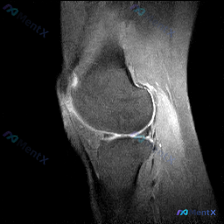

刚整理了一份很有启发的膝关节MRI读片病例,分享给大家,尤其能帮我们避避临床思维的坑。 病例核心影像信息 这是一例膝关节MRI T2序列矢状位影像,送检原因是怀疑存在半月板异常,系统评估各结构如下: 1. 骨骼关节软骨:股骨远端、胫骨近端、髌骨轮廓正常,股骨滑车和胫骨平台关节软骨大致平滑,无明显全层...